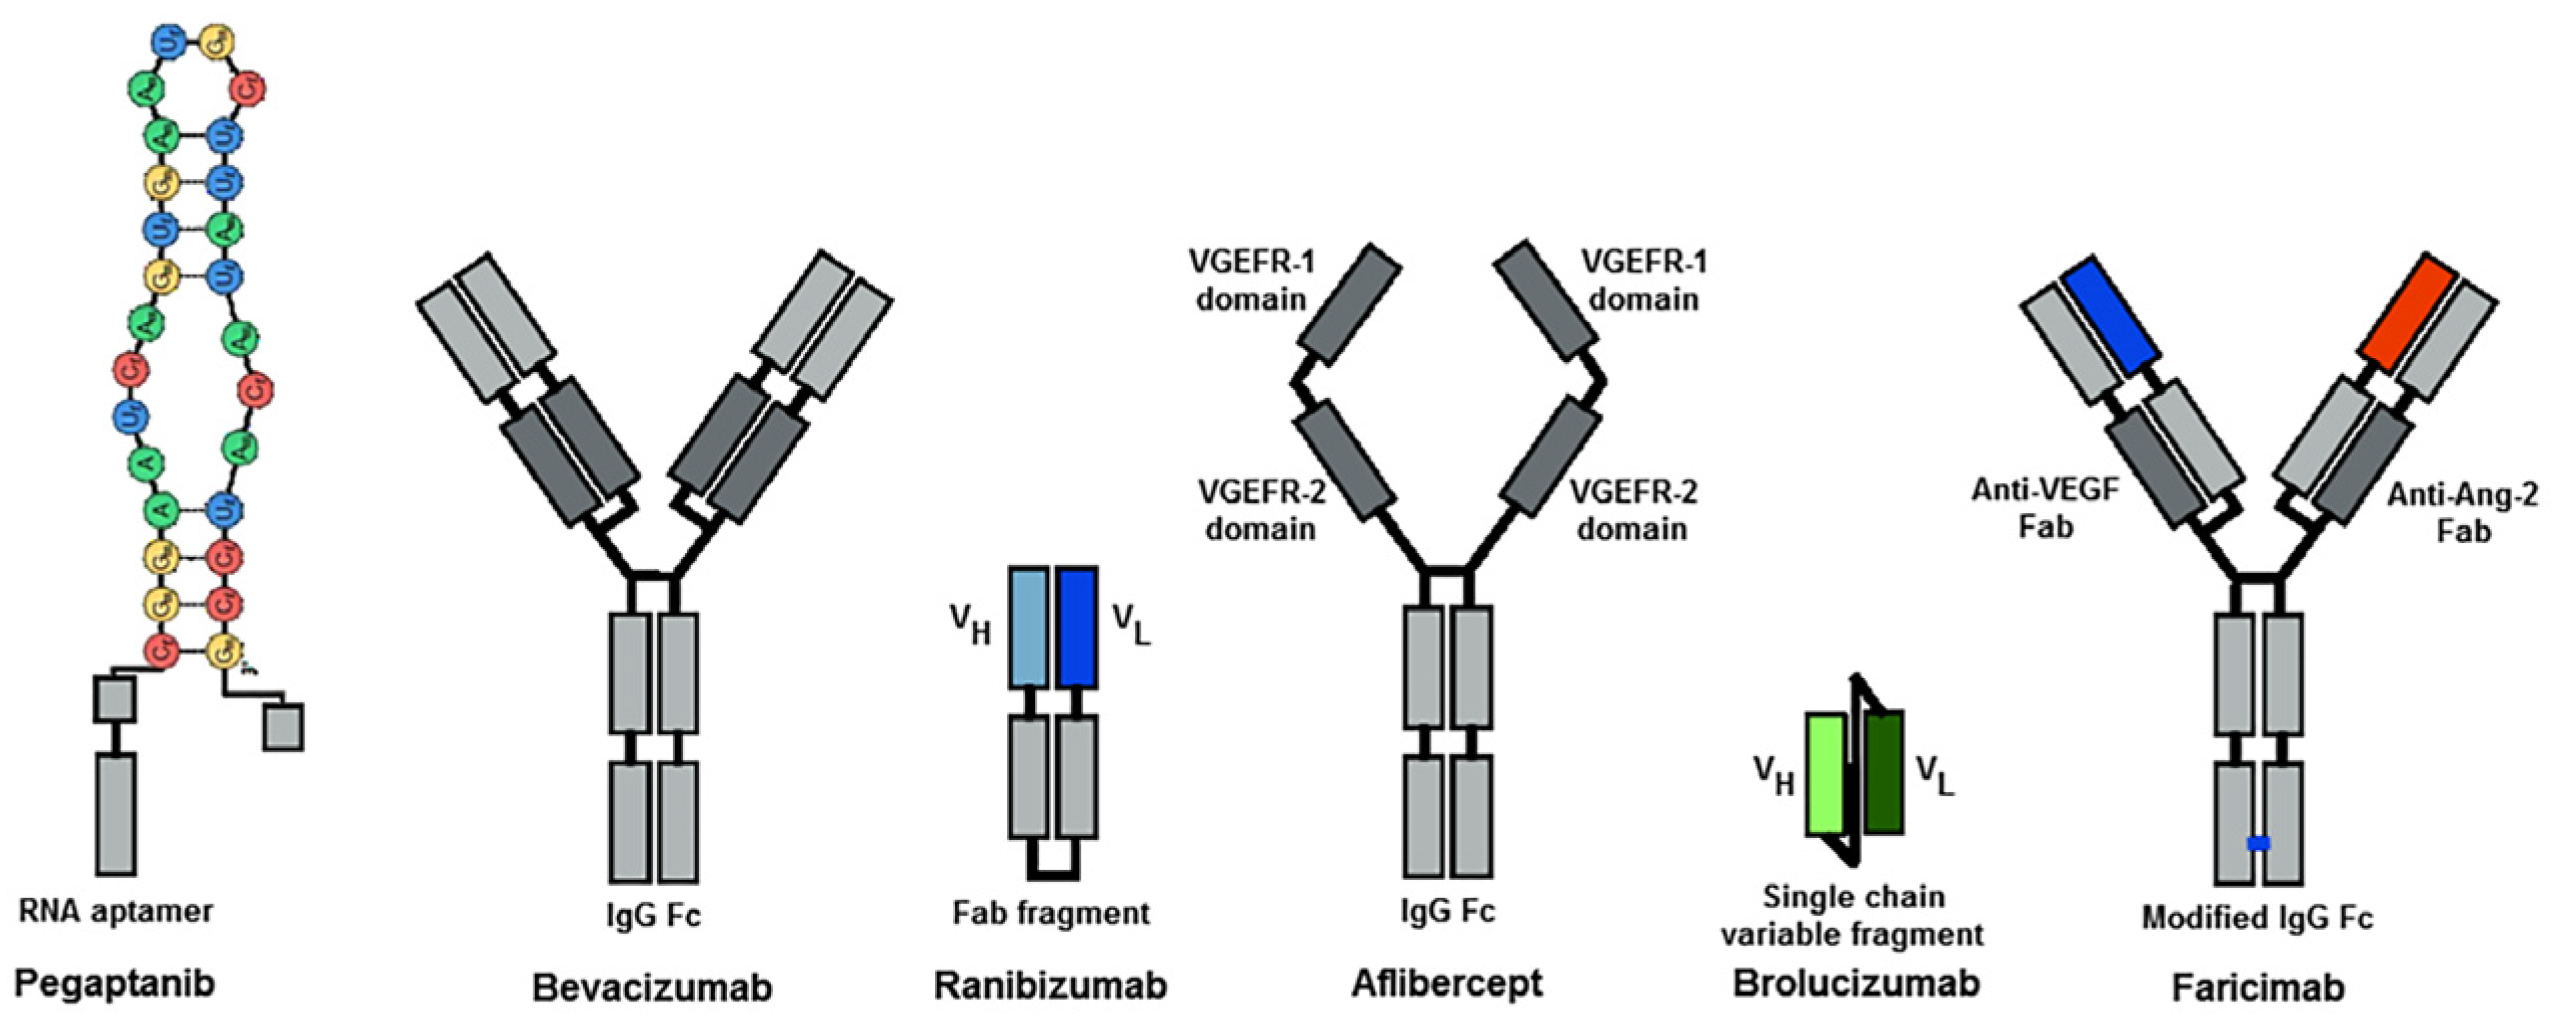

3.2. Anti-VEGF Drugs

3.2.1. General Information

3.2.2. Anti-VEGF Therapies

Pegaptanib

Bevacizumab

Ranibizumab

Aflibercept

Brolcizumab

Faricimab